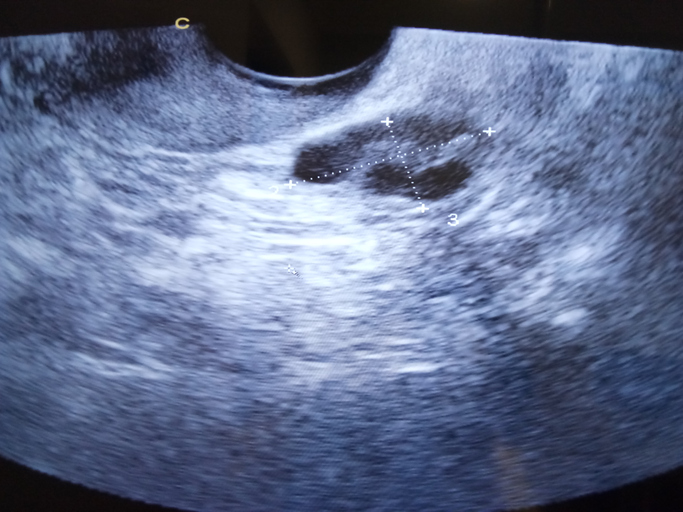

Il monitoraggio follicolare si esegue solitamente con visite regolari presso un medico specializzato in fertilità. Queste visite prevedono l’esecuzione di ultrasuoni periodici durante il ciclo mestruale. Comunemente per via transvaginale. In pratica si fanno delle ecografie, assolutamente non invasive e che non provocano dolore. Questi ultrasuoni forniscono immagini dettagliate dell’utero e delle ovaie, consentendo al medico di monitorare la crescita e lo sviluppo dei follicoli, con precise misurazioni. Inoltre, possono essere effettuati anche test ormonali ematici per valutare i livelli di estrogeni, di ormoni follicolo -stimolanti (FSH) e luteinizzanti (LH), che forniscono ulteriori informazioni sulla maturazione follicolare determinando il momento preciso dell’ovulazione. In genere le due metodiche si affiancano e completano, anche per avere una più precisa idea della fisiologia della donna, ovvero se sussistono problemi ovulatori di qualche tipo, da indagare più approfonditamente, anomalie uterine.